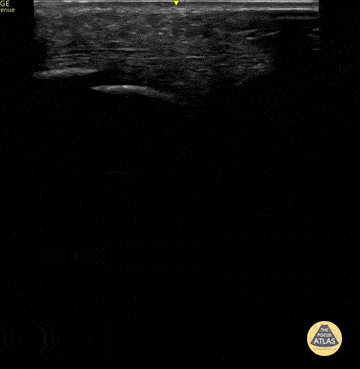

12 year old came in with a fall from a scooter and right lower leg pain and swelling, just above the ankle. POCUS was performed with a high frequency transducer in longitudinal axis of the area of swelling, which demonstrates the tibia as a discontinuous, displaced, hyperechoic linear structure with an associated mixed echotexture collection just anterior to the discontinuity, suggestive of a displaced tibia fracture with hematoma. Contributor: Allie Grither, MD, St. Louis Children's Hospital (Washington University in St. Louis), @AGPemMD